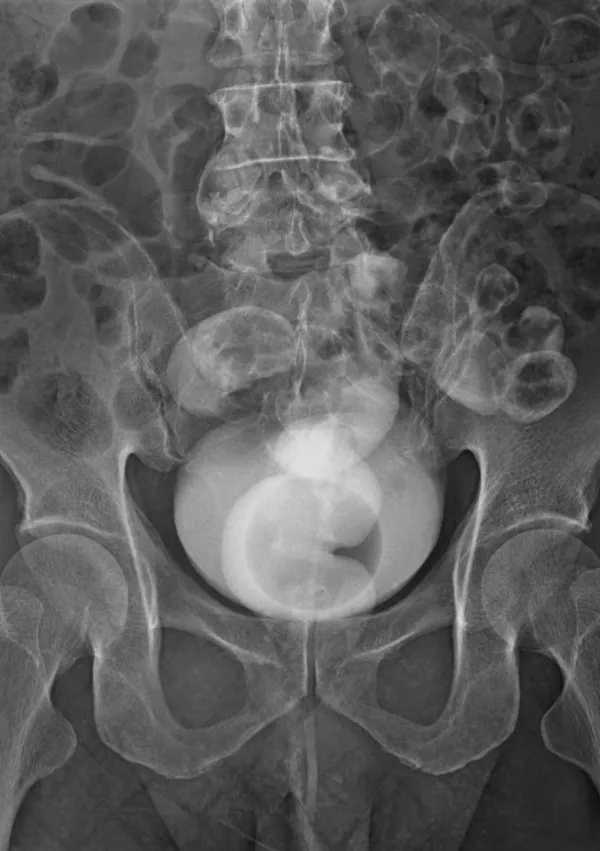

Rentgenska (simbolična) slika / Foto: Istock

Rentgenska slika / Foto: Istock